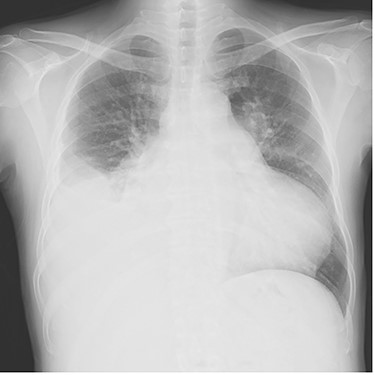

The patient was extubated on the third postoperative day. He was weaned off catecholamines on postoperative Day 9 and transferred from the intensive care unit on postoperative Day 10. Postoperative transthoracic echocardiography revealed no prosthetic valve dysfunction at either the aortic or pulmonary positions. Although his general condition was good, he had prolonged wound healing in the right inguinal region and resisted conservative treatment. Patchplasty of the right common femoral artery was performed on postoperative Day 49. He was discharged on postoperative Day 62. A plain radiograph from the first post-discharge outpatient visit is shown in Fig. 3. Two years postoperatively, the patient was doing well without heart failure.

Plain chest radiograph of the first outpatient visit after discharge from the hospital.